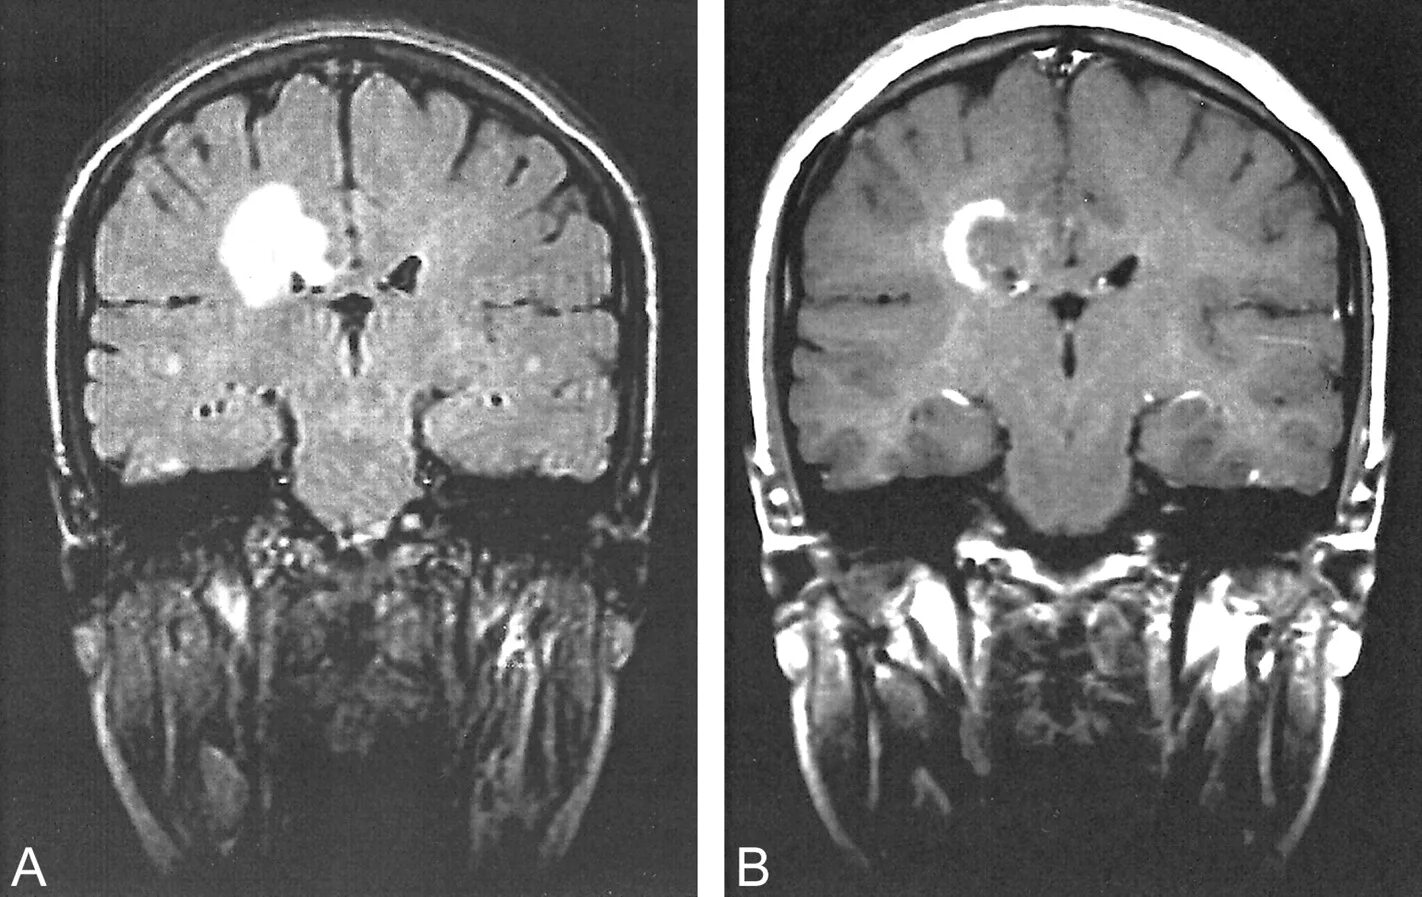

Энцефалит головного мозга симптомы у взрослых